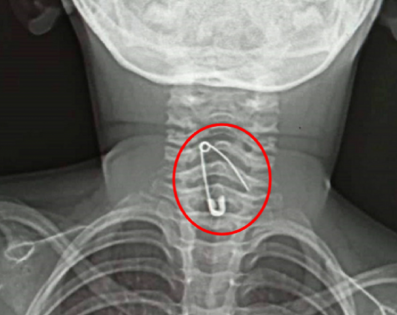

নুডলস খেতে গিয়ে শিশুর গলায় আটকে গেল সেফটিপিন!